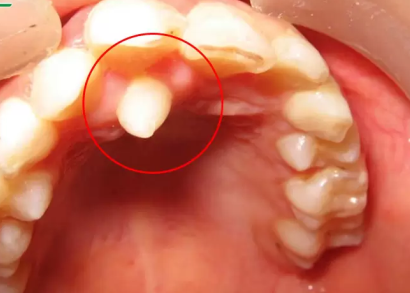

Răng thừa làm cho R21 mọc thưa và lệch về phía môi Răng thừa (a) làm R11 (b) bị kẹt không mọc ra được

Răng thừa gây nang xương hàm trên Răng thừa mọc vào tiền đình mũi

Hình 2: Một số biến chứng của răng thừa